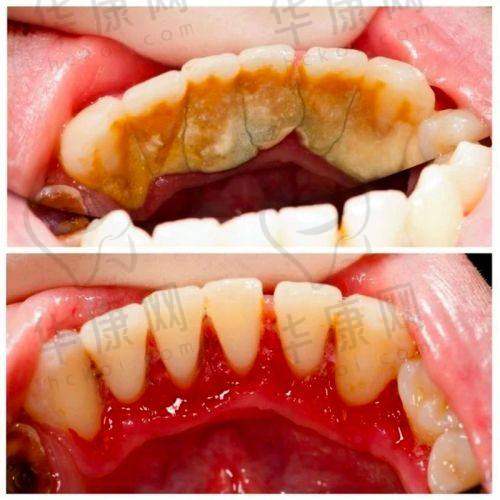

首先,医院环境舒适。走进宜春袁州春城口腔,干净整洁的环境让人放松,减少了患者看牙时的紧张感。这种舒适的环境有利于患者更好地配合医生进行喷砂洁牙等治疗。其次,医院注重设备的更新和维护。用于喷砂洁牙的设备都是精良且性能良好的,能够精细有效地去除牙齿表面的污垢、菌斑和色素,确保了洁牙的成效和安心性。此外,医院还定期邀请出名口腔医师来院坐诊。这些骨干医生可以为患者提供更加专精的口腔检查和个性化的治疗方案,对于在喷砂洁牙过程中可能遇到的特殊情况,能够给予更科学的处理。

医院内的医生全部持证上岗,拥有丰富的口腔诊疗经验。在喷砂洁牙领域,他们能够熟练操作设备,根据患者牙齿的不同状况调整喷砂的力度和范围。比如,对于牙齿敏感的患者,医生会更加轻柔地操作,避免给患者带来不适。而且,医生们不仅在洗牙等基础项目上表现出色,更在牙齿种植、牙齿矫正、美学修复等高端领域有着深厚的造诣。这使得他们在进行喷砂洁牙时,能够从整体口腔健康和美观的角度出发,为患者提供更全方面的建议。例如,在洁牙过程中发现患者有龋齿等问题,医生会及时告知并给出相应的治疗方案。